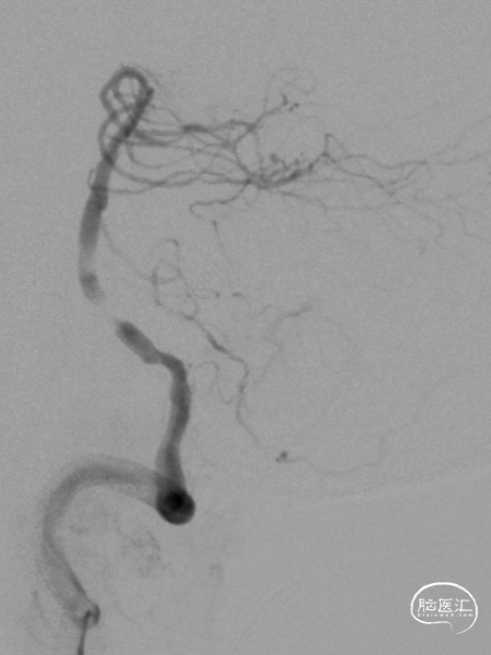

临床上常遇到基底动脉近端闭塞,后交通发达,远端存在前向后代偿病例。部分患者早期桥脑小片状梗死,NIHSS非常低,但容易在数天内逐渐缓慢进展。请问此类患者的介入时机如何把握?

举例图片,非上述病例患者